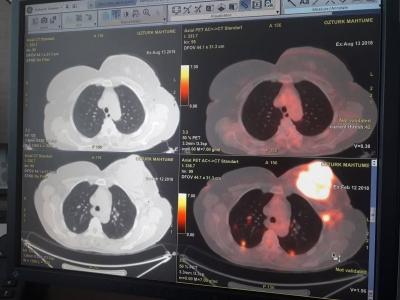

من أجل تطوير المهارات الفنية للتدريسيين، أوفدتْ جامعة الموصل التدريسية في فرع الطب الباطني كلية الطب جامعة الموصل المدرس الدكتورة علياء عبدالعزيز نجم (دكتوراه سريرية في طب الأورام والعلاج الإشعاعي) من أجل الاشتراك بدورة تدريبية على التقنيات الحديثة للعلاج الاشعاعي للاورام، وذلك للفترة من 29 تموز 2018 لغاية 24 آب 2018. ولقد أُقيمت الدورة المذكورة في مستشفى رياب التخصصي التابعة لجامعة روميلي في مدينة اسطنبول التركية. وقد تمّ التدريب على جهازTrueBean Varian For Radiotherapyالمعجل الخطي المتطور. ويعد هذا الجهاز من احدث اجهزة العلاج الاشعاعي للاورام؛ إذ يستخدم تقنية العلاج الاشعاعي التجسيميSRS Stereotactic Radiosurgeryوالعلاج الاشعاعي الستيروتاكتيكي للجسمSBRT Stereotactic body radiotherapy. ويوفر هذا العلاج الاشعاعي جرعات عالية من الاشعة المحورية عبر توجه الاشعاع الى الورم بدقة عالية من خلال جلسة واحدة فقط، أو عدد محدود من الجلسات، من دون التاثير على الانسجة السليمة المحيطة للورم. ومما يذكر في هذا الصدد أن التصوير المقطعي بالاصدار البسترونيPET-CT Positron Emission Tomography يعد تقنيةَ تصويرٍ ثلاثية الإبعاد (في الطب النووي)؛ إذْ تتيحُ هذه التقنية تبيان اعضاء الجسم وما قد يكون فيها من ورم سرطاني او نقيلات سرطانية. كما يمكن بواسطتها تفقد مختلف العمليات الوظيفية في الجسم.